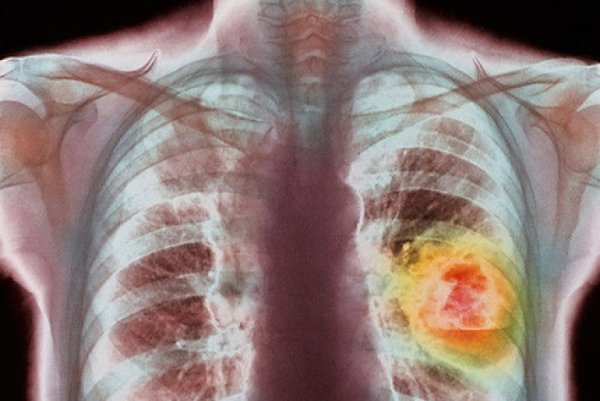

Рентгеновское исследование легких требуется для определения местонахождения раковой опухоли.

Реконструктивная томография делается для выявления наличия метастазов в организме. Также с помощью этого метода можно точно определить стадию протекания болезни.